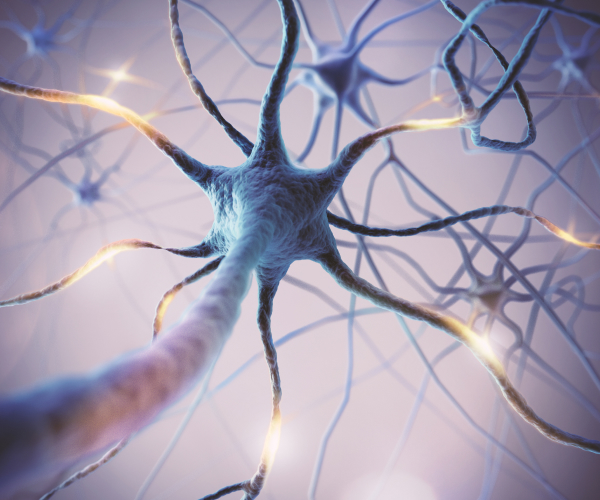

신경이 눌리면서 발생하는 통증

추간판이 퇴행성 변화나 약해진 허리근력으로 인해 강한 충격을 완충하지 못하게 되면, 신경이 압박되어 저림 증상 등이 발생될 수 있습니다.

02

허리디스크와는 다른 척추관 협착증

신경이 지나가는 척추 중앙의 관이 좁아져 허리 통증을 유발하거나 다리 신경 증세를 일으키는 질환으로 주로 운동량이 많은 허리와 목 부위에 많이 발생합니다.